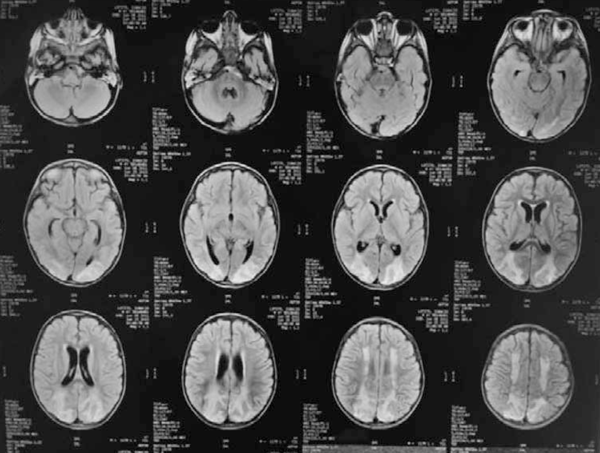

Ecocardiograma con Doppler: fallo contráctil de ventrículo izquierdo que mejora con diuréticos e inotrópicos. RNM de cráneo (Figura 3) evidencia extensas lesiones cortico-subcorticales bilaterales en centro oval y fronto-parietales homogéneas con áreas hipo e hiperintensas en T1, T2 y Flair, con espacios de restricción de difusión y realce gírico con el contraste. Ventrículos de amplitud ligeramente aumentada, al igual que los espacios subaracnoideos.

Permaneció internado 48 días, mejorando progresivamente las alteraciones clínicas y paraclínicas, destacándose la afectación neurológica con hipertonía de los cuatro miembros, hiperreflexia, clonus agotable al estímulo y hemiparesia de hemicuerpo derecho. Luego de logrado el destete de la ventilación, se mantuvo vigil, sin ningún vínculo con el ambiente, en posición fetal, planteándose además de la encefalopatía vinculada a la LH la posibilidad de un síndrome de encarcelamiento o posinternación en CTI iniciándose risperidona con buena respuesta cognitiva, manteniendo el compromiso motor sobre todo de miembros inferiores. Potenciales evocados auditivos y visuales normales.